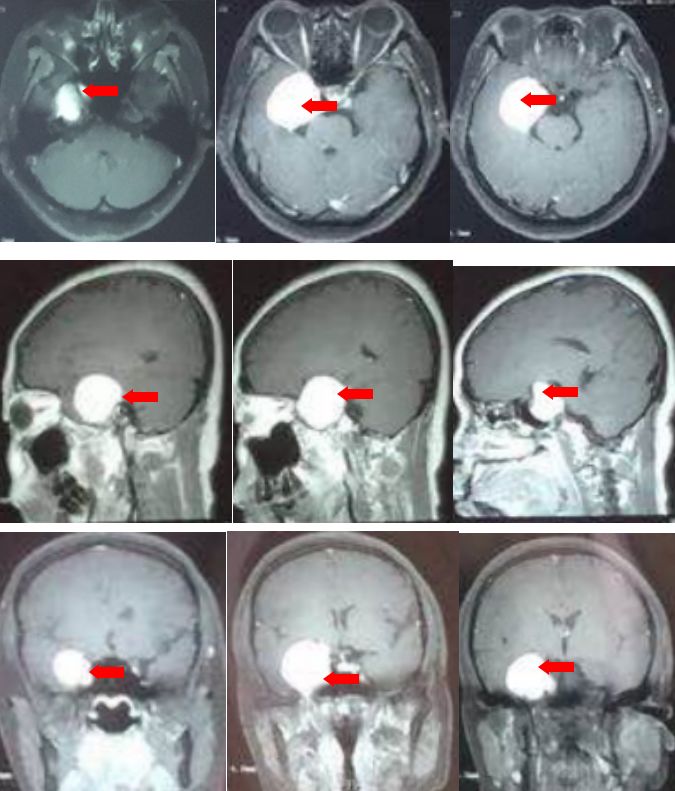

颅脑核磁平扫加增强:右侧海绵窦区可见类圆形长T1长T2信号,增强可见均匀强化,大小约36x41x35mm,病灶边缘清晰,无含铁血黄素带,周边脑组织无明显水肿表现,右颈内动脉海绵窦段部分包绕。

颅脑核磁T1W1成像

颅脑核磁T2W1成像

颅脑核磁增强扫描

根据影像学特点,诊断为海绵窦内巨大海绵状血管瘤可能性大。